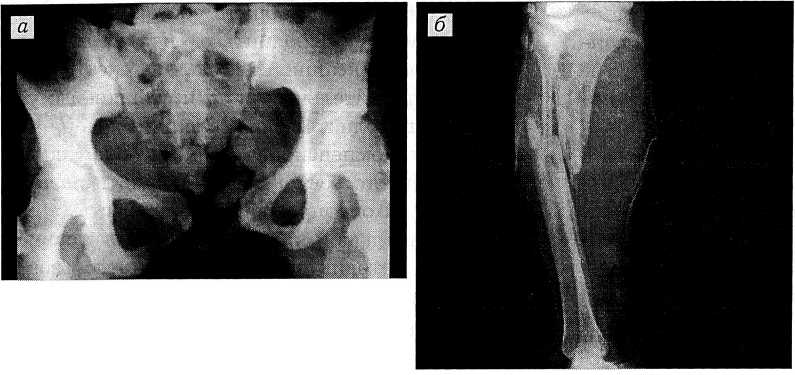

Рис. 1. Прямая обзорная переднезадняя рентгенограмма таза (а) и рентгенограмма правой голени (б) больной Б. при поступлении.а — разрыв лобкового симфиза с диастазом до 6 см и левого крестцово-подвздошного сочленения; б — многооскольчатый двойной открытый перелом костей голени.

В операционной на фоне противошоковых мероприятий проведено клиникорентгенологическое обследование. При лапароскопии обнаружена кровь в брюшной полости. Рентгенологически выявлены разрыв лобкового симфиза с диастазом до 6 см и левого крестцово-подвздошного сочленения, многооскольчатый перелом обеих костей правой голени в верхней— средней трети (рис. 1).